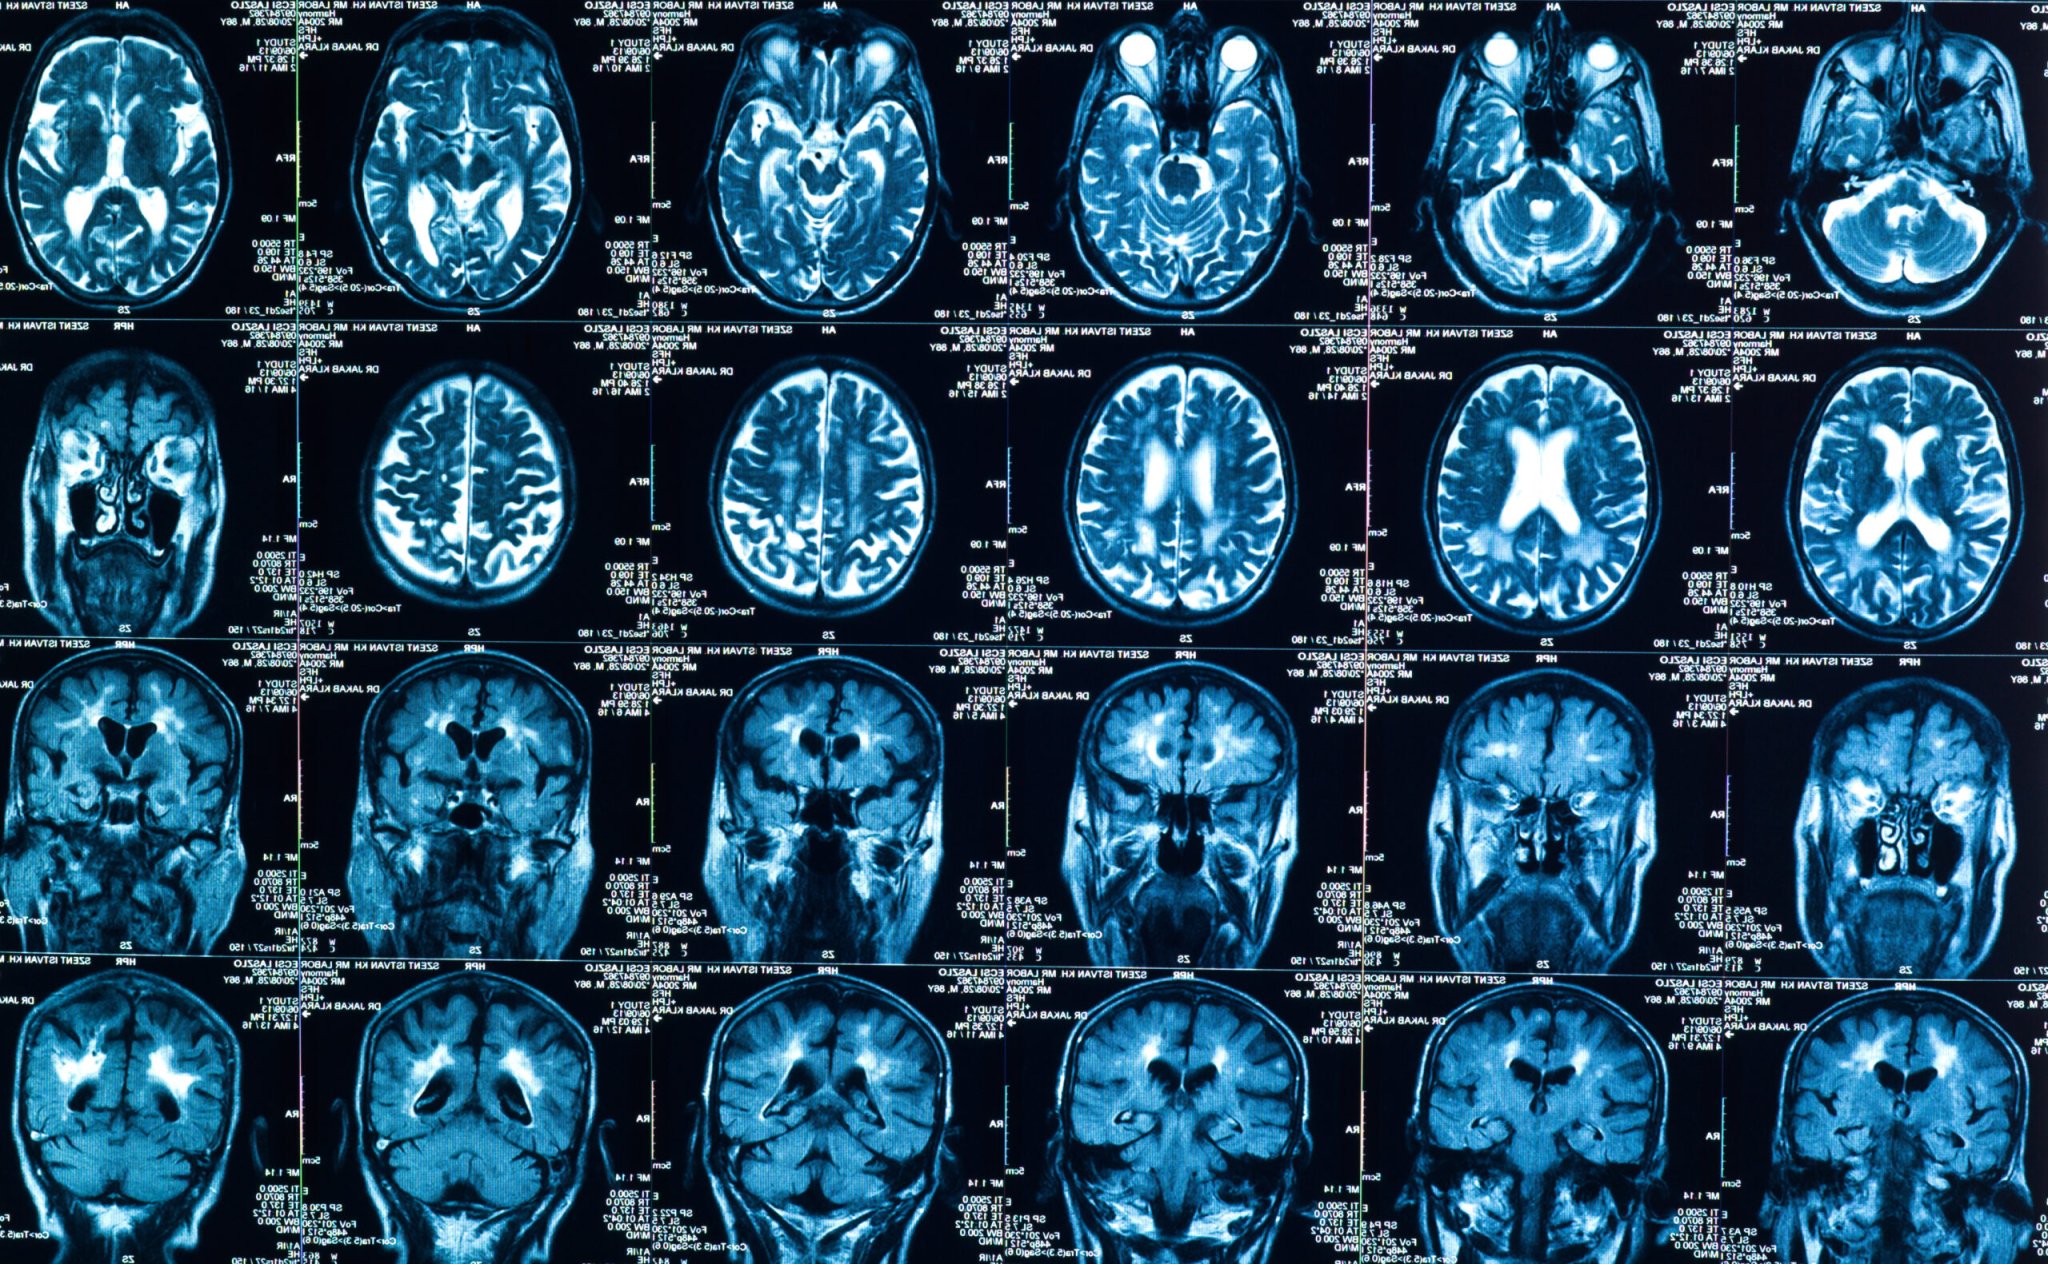

Most of the information about the progression of tumors in cancer patients is contained in written notes from radiologists, who examine scans and track changes in the status of the cancer. Because it’s raw text—not choices from a drop-down menu or data points in a spreadsheet—most analytic methods can’t pull the relevant information. The tool created in this study leveraged improvements in machine learning for language to identify those details in electronic health records.

For this particular tool, the scans from cancer patients were initially read by human radiologists. But artificial intelligence and machine learning can read images, as well, and research shows that they can analyze scans of tumors as effectively as human radiologists. In another study published this month, radiologists and artificial intelligence experts partnered to develop an algorithm that could determine if lumps on a thyroid should be biopsied—and found that recommendations from the machine learning tool recommended biopsies similarly to expert radiologists using the American College of Radiology (ACR) system.

Visual analysis is further along in medicine and oncology than textual analysis, Kehl says, but both could be components of integration of machine learning into the normal practice of care. It might be possible, for example, to integrate machine interpretation of scans into the overall electronic health record analysis, he says. “That would mean looking at how much information we get from images themselves, how much do we get from human interpretation, and what could we get from the model looking at images,” he says. “The optimal strategy still isn’t known.”